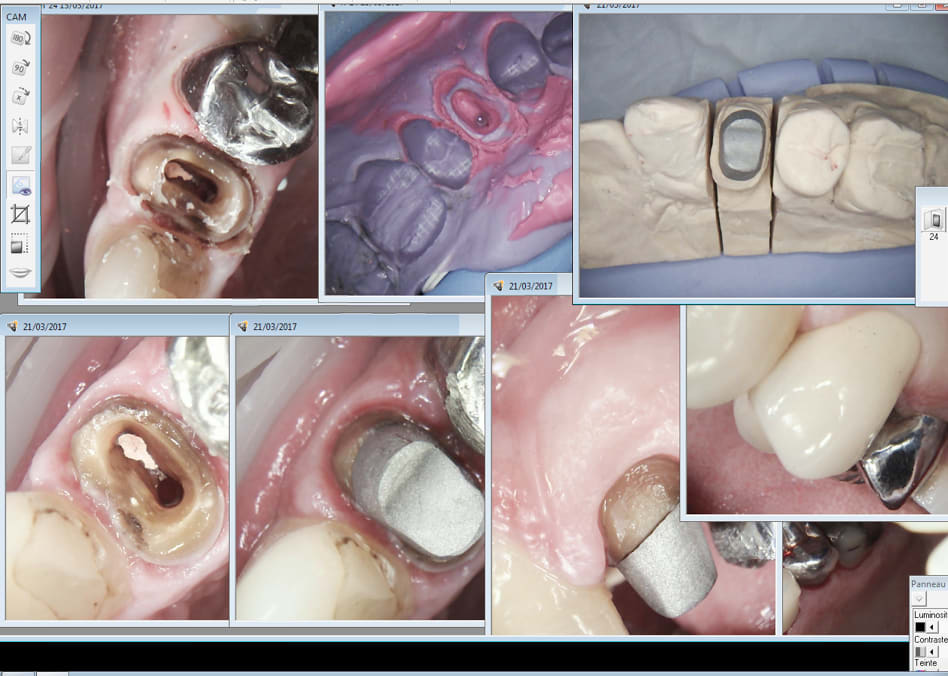

Eviction marginale laser. Temporisation clip flow. Une semaine après pose.

C'est marrant tu vois à peine les congés en bouche mais mieux sur les empreintes.